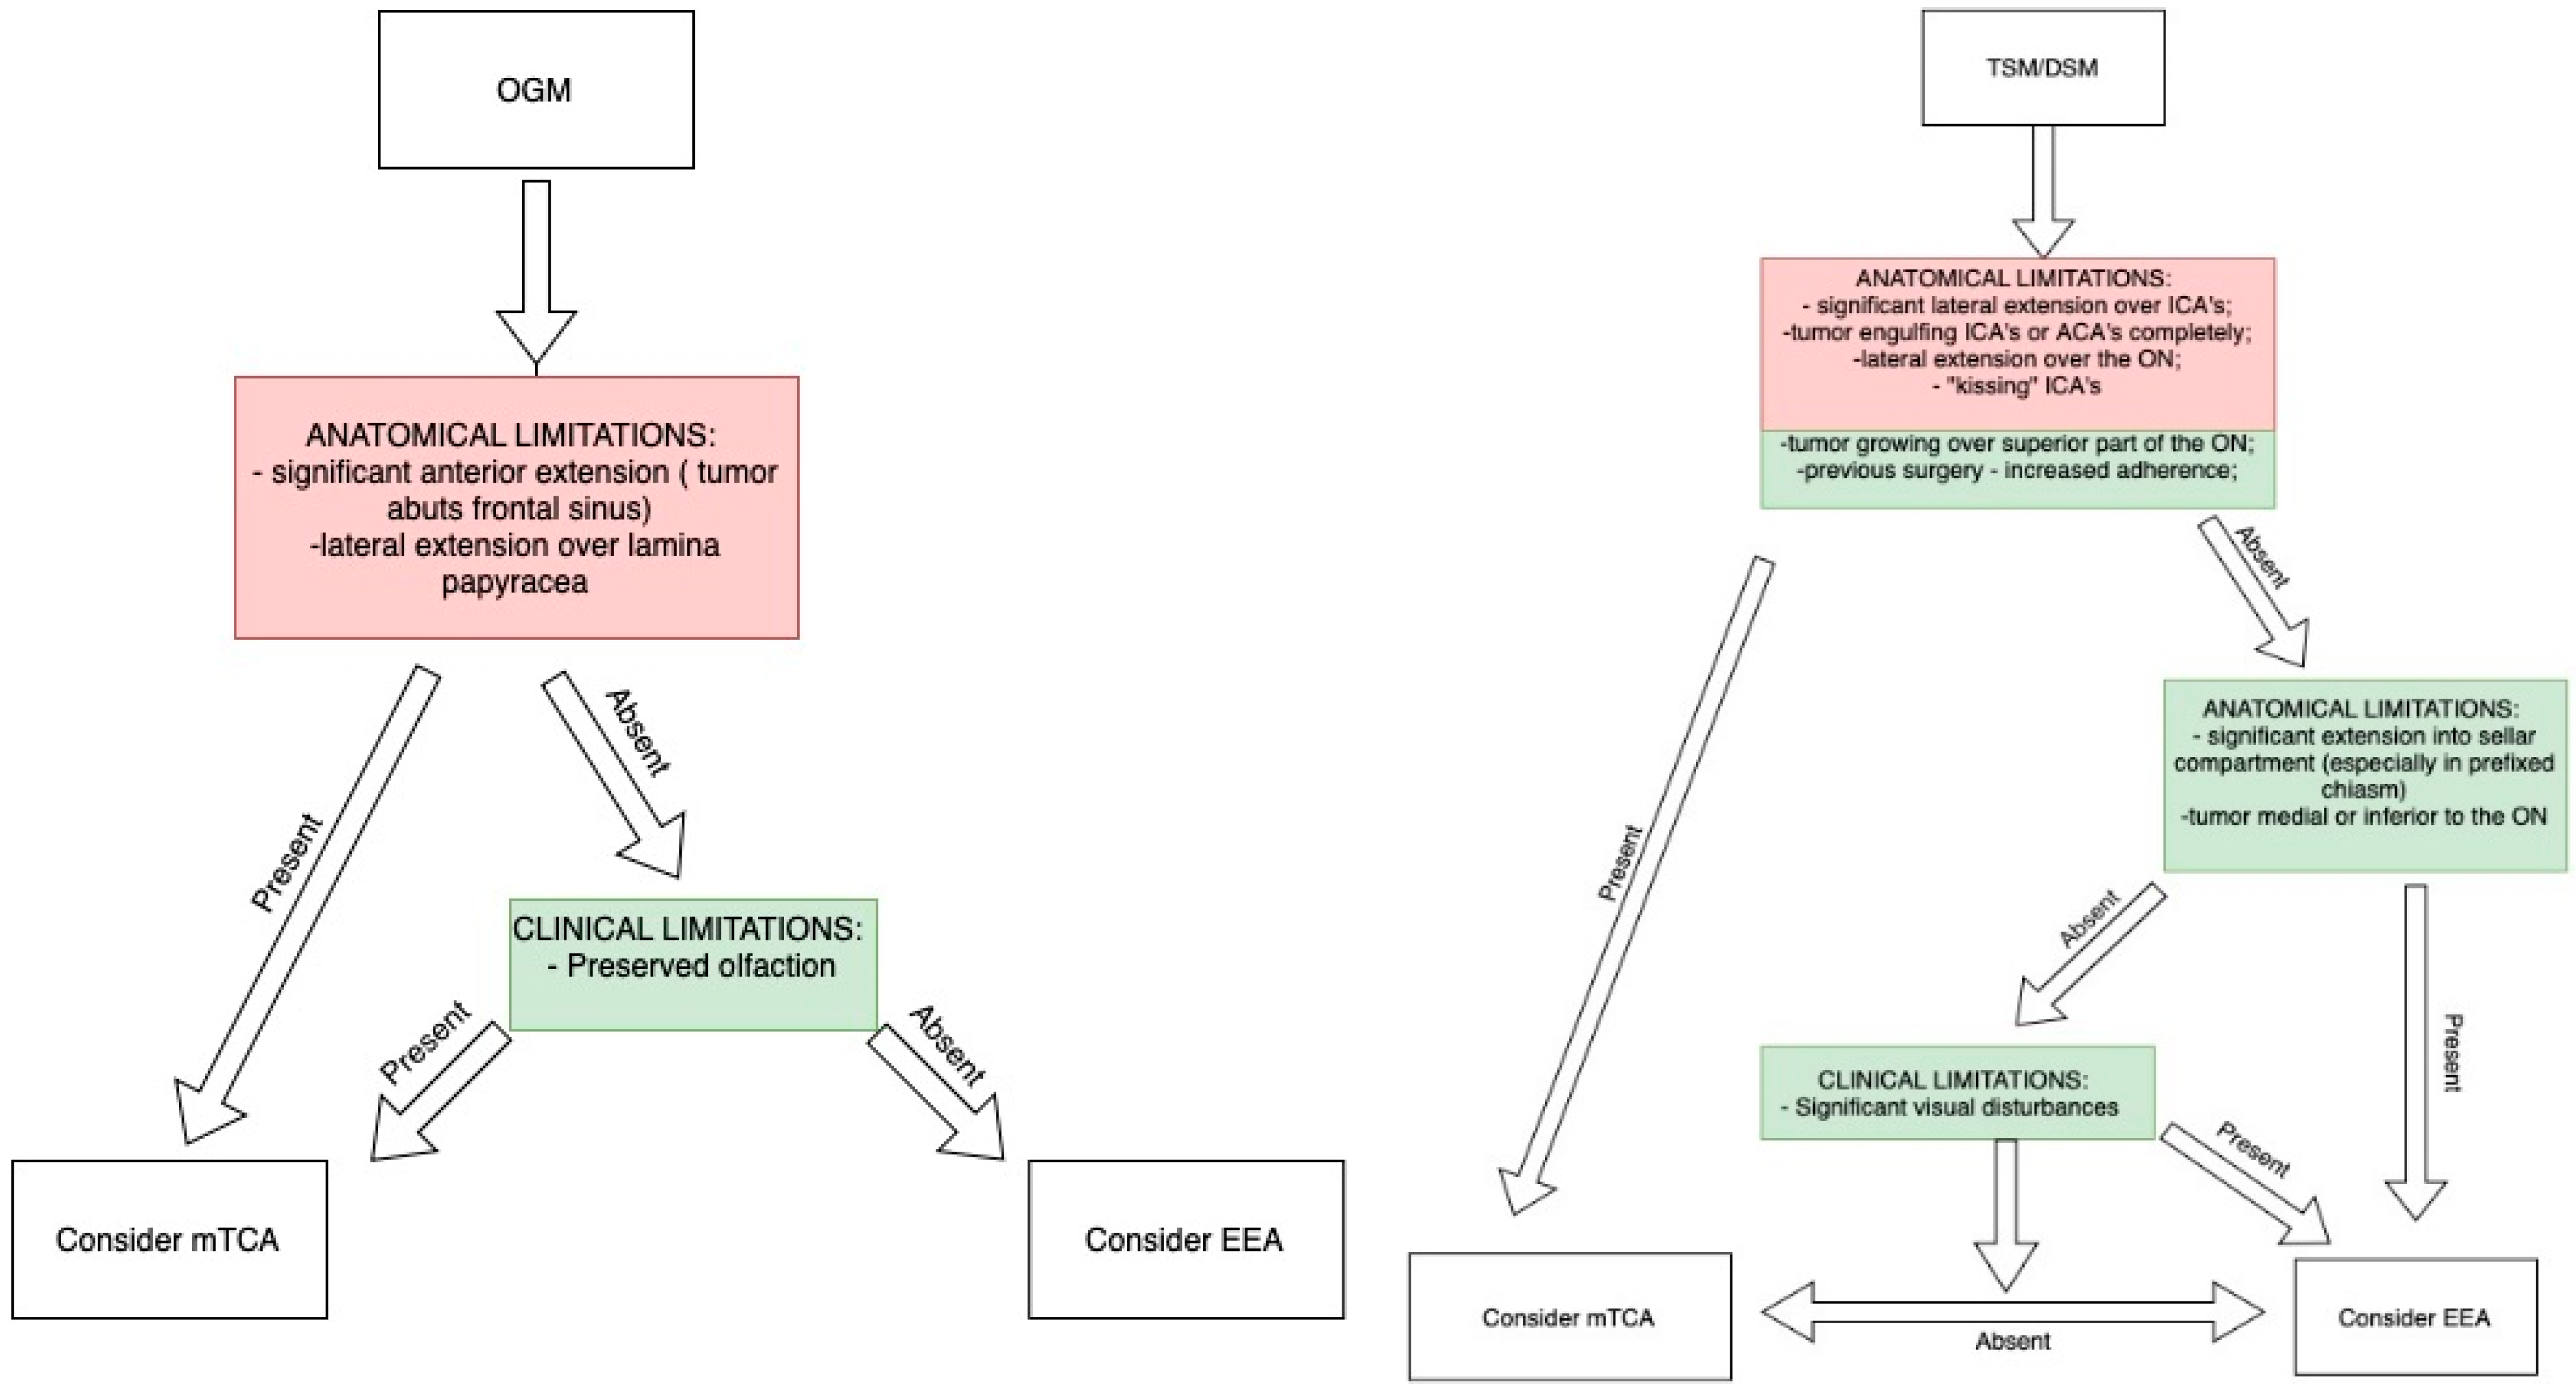

9. Importance of Preoperative Imaging and Clinical Characteristics for Approach Selection

- Approach Selection: The frontolateral approach balances exposure and safety for tumors without significant extradural extension. The EEA is best for visual preservation in tumors without extensive lateral extension and without vascular encasement.